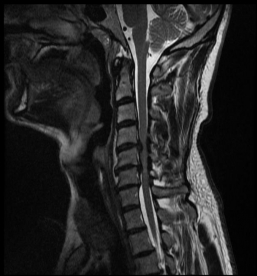

Spinal stenosis can also occur in the cervical spine. In this case, an orthopedist should be consulted at an early stage due to the risk of a spinal cord lesion. Warning signs can be, for example, the regular dropping of objects or gait difficulties with the feeling of "drunken walking". If such a spinal cord lesion has already occurred or is increasing, surgery should be discussed openly.

MRI with lateral reconstruction of the cervical spine and a lateral postoperative radiographic check. On the left, an hourglass-shaped constriction of the spinal cord can be seen. The right image shows the condition after surgical decompression and stabilization.